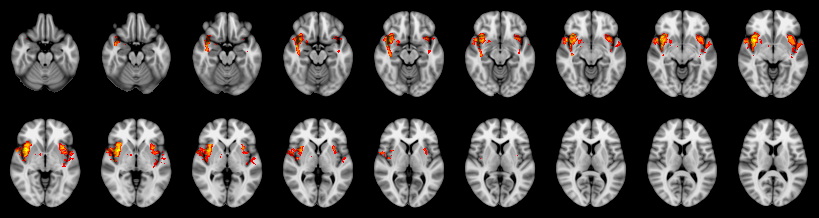

Pain study, TFCE, Corrected

Not combined

Face:

Hand:

Foot: